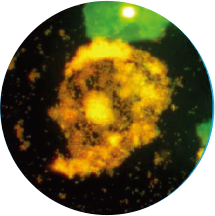

免疫荧光法结果展示及判读示例

阴道分泌物多重免疫荧光染色技术,具备形态学与荧光学的双重优势。可以同时对上皮细胞,白细胞,乳酸杆菌,线索细胞,念珠菌和毛滴虫等进行染色区分,既能检测阴道相关病原体感染,也能评估其阴道微生态和阴道清洁度等是否正常,为临床的快速诊断和治疗提供帮助。

线索细胞

橙黄色荧光

边缘不规则,模糊大小

与上皮细胞一致